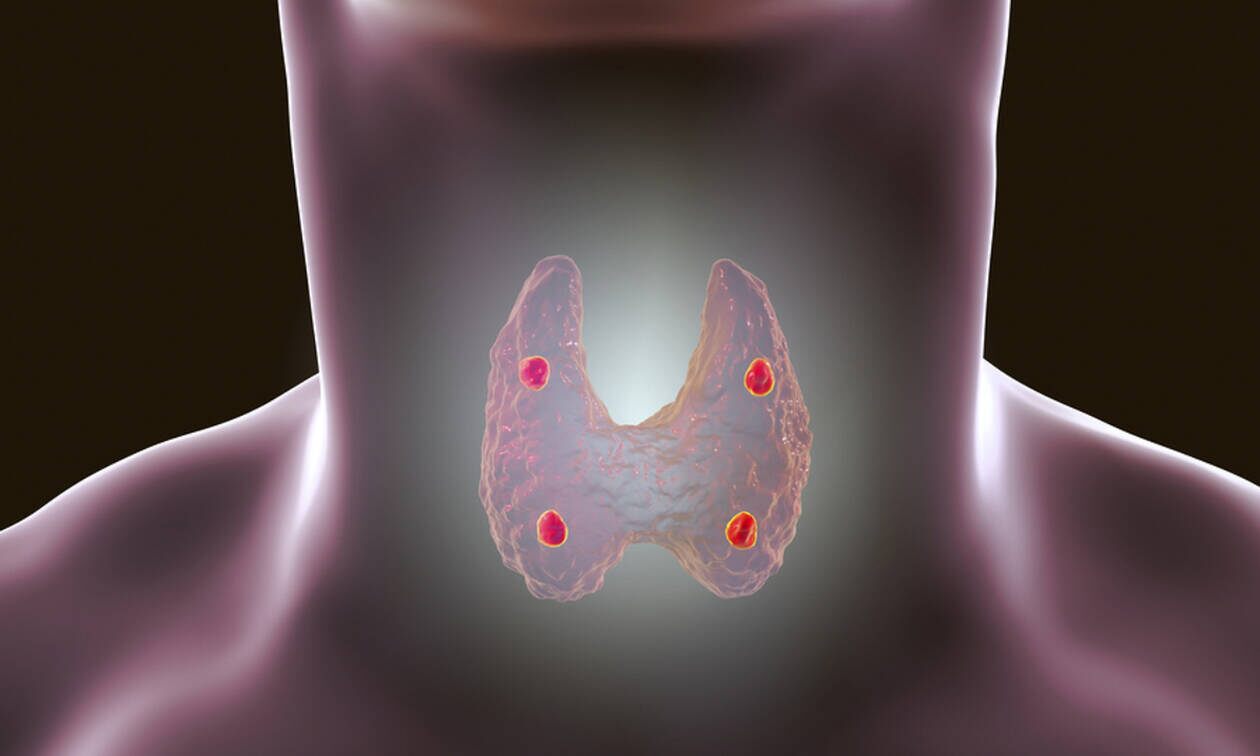

Έχετε αναρωτηθεί ποτέ μήπως η διατροφή μας προκαλεί κακό στον θυρεοειδή μας; Ή μήπως ορισμένες τροφές μπορούν να επιδεινώσουν την κατάσταση για έναν ασθενή που αντιμετωπίζει προβλήματα με τον θυρεοειδή του;

Ας ρίξουμε μια ματιά στις πιο επικίνδυνες τροφές, και πώς μπορούμε να τις καταναλώσουμε με ασφάλεια:

Σταυρανθή λαχανικά

Τα λατρεμένα μας σταυρανθή, όπως το μπρόκολο, το κουνουπίδι και τα λαχανάκια Βρυξελλών, περιέχουν μια ουσία που εμποδίζει την σωστή απορρόφηση ιωδίου, συνεπώς δεν ενδείκνυνται ωμά για ασθενείς με προβλήματα στον θυρεοειδή. Το μαγείρεμα, όμως, τα κάνει πιο ασφαλή για κατανάλωση, και μπορούν να αποτελέσουν κομμάτι μιας ισορροπημένης διατροφής.

Σόγια

Η σόγια μπορεί να μπλοκάρει την απορρόφηση θυρεοειδούς ορμόνης, ειδικά αν πάσχετε από υποθυρεοειδισμό. Καλύτερα θα ήταν να μην το παρακάνετε με προϊόντα σόγιας, και να προτιμάτε τόφου. Αποφύγετε τις σκόνες για shakes, όπως και το γάλα σόγιας.

Καφές

Μην ανησυχείτε, μπορείτε να συνεχίσετε να πίνετε καφέ, αλλά με προσοχή. Αν παίρνετε χάπια για την πάθησή σας, όμως, δεν πρέπει να τα μπλέκετε με καφέ, καθώς περιέχει ένα οξύ που εμποδίζει την απορρόφηση των φαρμάκων από τον οργανισμό. Συνεπώς, περιμένετε τουλάχιστον μία ώρα μετά τα φάρμακά σας για να πιείτε καφέ, ακόμα και αν είναι ντεκαφεϊνέ.

Γάλα

Αν πάσχετε από υποθυρεοειδισμό, το ασβέστιο που βρίσκουμε στο γάλα μπορεί να εμποδίσει την σωστή απορρόφηση των φαρμάκων σας. Συνεπώς, δεν πρέπει να καταναλώνεται τρεις με τέσσερις ώρες αφού έχετε πάρει τα φάρμακά σας.

Γλουτένη

Η γλουτένη είναι μια πρωτεΐνη που επηρεάζει αρνητικά ένα μικρό μέρος του πληθυσμού: όσους πάσχουν από κοιλιοκάκη, και όσους έχουν δυσανεξία σε αυτήν. Πιστεύεται όμως ότι τα άτομα με υποθυρεοειδισμό θα ήταν καλό να περιορίσουν ή και να κόψουν την γλουτένη από την καθημερινότητά τους.

Τροφές που προκαλούν φλεγμονές

Οι φλεγμονές παίζουν μεγάλο ρόλο στα προβλήματα του θυρεοειδούς, και με το να αποφεύγουμε τις τροφές που μας τις προκαλούν, κάνουμε ένα μεγάλο βήμα για μια καλύτερη ζωή. Συνεπώς, μερικά από τα συστατικά που πρέπει να αποφεύγετε, είναι η ζάχαρη, τα λευκά αλεύρια, τα συντηρητικά, τα επεξεργασμένα κρέατα και τα τρανς λιπαρά. Αυτό σημαίνει ότι πρέπει να αποφεύγετε και τα τηγανιτά.

Τεχνητά γλυκαντικά και αναψυκτικά

Τα αναψυκτικά που χαρακτηρίζονται light περιέχουν υποκατάστατα ζάχαρης, τα οποία μπορεί να μην μας φορτώνουν με περιττές θερμίδες, αλλά μπορεί να δημιουργήσουν προβλήματα στη λειτουργία του θυρεοειδούς και του ανοσοποιητικού συστήματος.